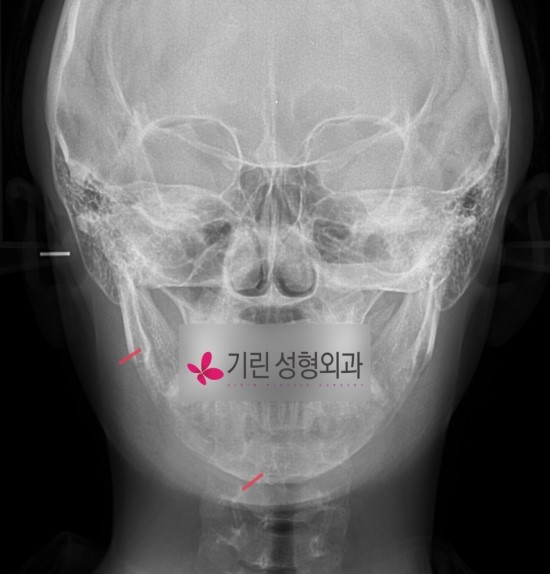

(귀밑각부터 턱끝까지 한번에 절골)

기린의 긴곡선브이라인은 귀밑각부터 턱끝까지 한번에 절골합니다.

아래에 붉은선으로 표시된 부분이 잘라낸 사각턱범위입니다.

턱끝까지 잘라내기 때문에 앞턱수술이 따로 필요없고

T절골이나 일자절골(샌드위치절골)에 비해

수술시간이 빠르고 조직손상도가 낮아 부기회복이 빠릅니다.

엑스레이 사진에서 보이는 붉은색으로 표시된 부분만큼(턱끝까지) 절골되었으며

원하는 브이라인 정도에 따라 귀밑각을 남기거나(자연스러운 라인) 뾰족한 브이라인이 가능합니다.

단, 신경선의 위치에 따라 수술이 가능한 범위의 한계가 있기 때문에

엑스레이촬영이나 CT촬영후 상담을 받아보는 것이 정확합니다.